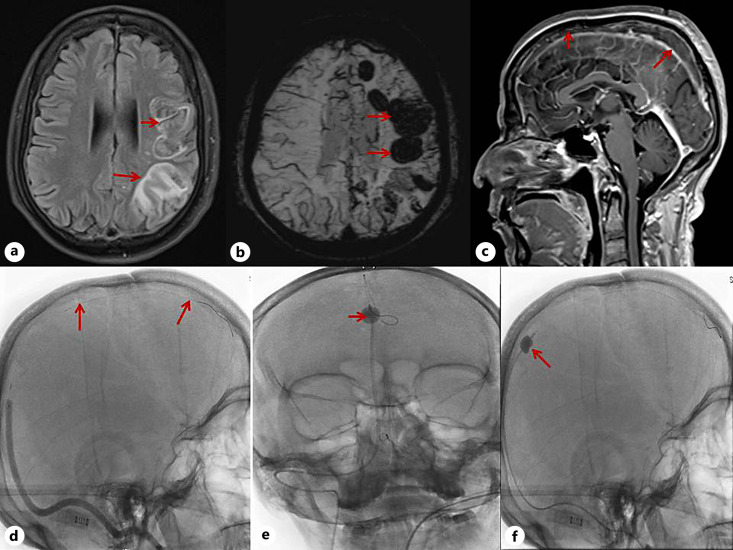

Abstract Image